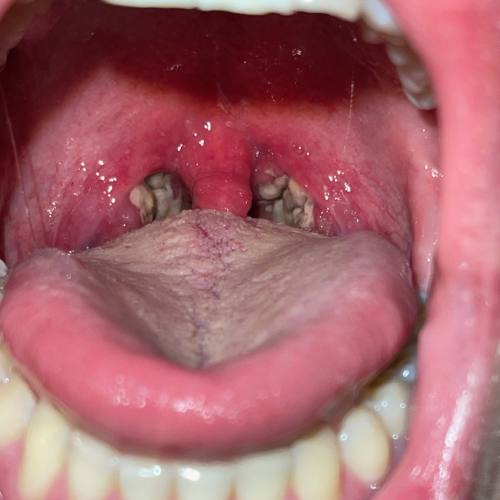

Mandelsteine (Tonsillensteine), wenn es zu kleinen, weißlichen Ablagerungen an den Mandeln kommt.

Mandelsteine sind als ca. 3–4 mm große, weiß-gelbliche Flecken (Erhebungen) auf den Gaumenmandeln erkennbar. Die Konsistenz variiert zwischen weich und hart.